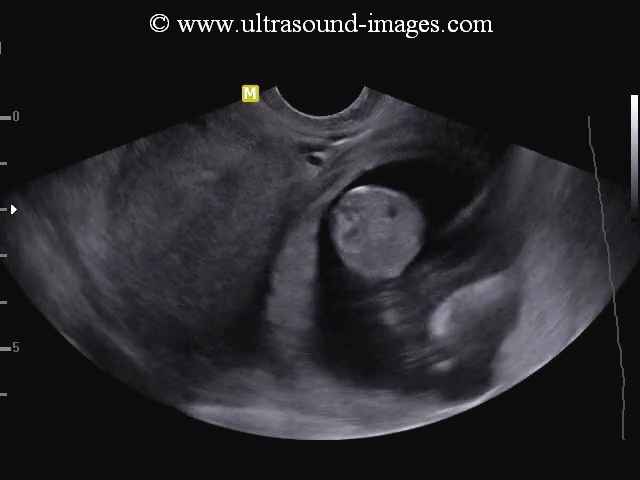

Cornual pregnancy

Sonography of the uterus shows a gestation sac of 6 weeks 4 days age, in the right cornu of the uterus. 3-D image of the uterus further confirms the findings. These ultrasound images are diagnostic of cornual pregnancy (a type of ectopic pregnancy). Ultrasound images courtesy of Dr. Latha Natrajan, Bangalore, India.